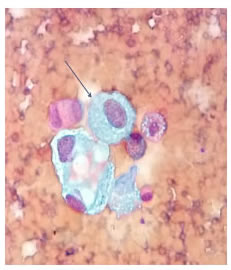

Se realizó una ventana pericárdica más pericardiectomía e instalación de un catéter pleuro-pericárdico subcutáneo (tunnelized) mediante toracoscopia izquierda. El líquido pericárdico era de color cetrino. No se identificó carcinomatosis pleural o pericárdica. El examen citológico del líquido pericárdico fue negativo para neoplasia maligna y en la histopatología de las biopsias de pericardio y de pleura parietal se observó un mesotelio reactivo, negativo paraneoplasia maligna (figura 3).

El estudio citológico del líquido pericárdico y del bloque celular mostró características serohemáticas; fue positivo para neoplasia maligna: carcinoma (figura 8). La histopatología del tejido obtenido de la ventana pericárdica fue negativa para neoplasia maligna.

En el estudio citológico y del bloque celular del líquido pericárdico, se reportó neoplasia maligna: carcinoma. En la histopatología del pericardio se informó adenocarcinoma de mama. En la inmunohistoquímica, los receptores de estrógeno y de progesterona, la proteína GATA y la mamoglobina, fueron positivos, y el protooncogén HER2/neu, negativo (figura 12).